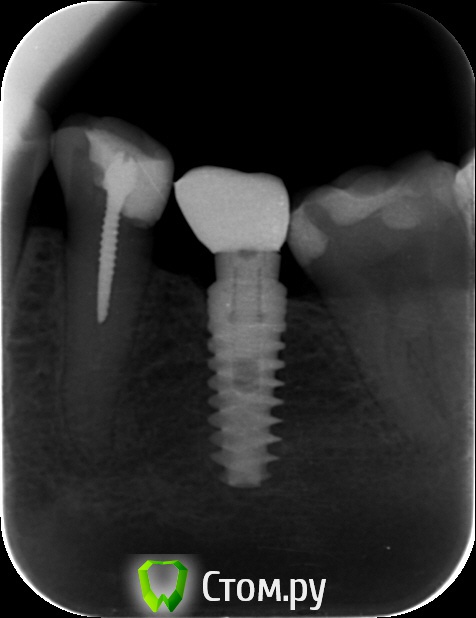

an_ver Опубликовано 29 мая, 2014 Поделиться Опубликовано 29 мая, 2014 Кто то пытался достать))) Абатмент спили в ноль...головку винта своротили.Набор Нео 3 Ссылка на комментарий

molchanoff Опубликовано 29 мая, 2014 Поделиться Опубликовано 29 мая, 2014 анкерок в пятерке в нерве стоит. Ссылка на комментарий

an_ver Опубликовано 29 мая, 2014 Автор Поделиться Опубликовано 29 мая, 2014 анкерок в пятерке в нерве стоит.Ага))) пациентка говорит лет 10-15 как стоит))) Ссылка на комментарий